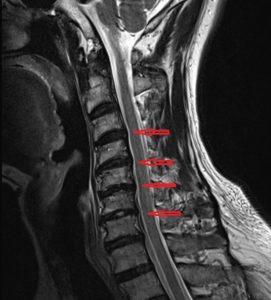

급성 경추 추간판 탈출증 (급성 경추 디스크)

급성 경추 추간판 탈출증 (급성 경추 디스크) 안녕하세요. 오늘은 급성 경추 추간판 탈출증, 흔히 말하는 경추 디스크에 대해 말씀드리겠습니다. 고래한의원 원장 박대명입니다. ‘급성 경추 추간판 탈출증’은 갑작스럽게 발생하는 강한 목...